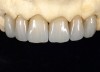

Fig 1. Preoperative extraoral view of a patient’s smile exhibiting compromised esthetic situation.

Figure 1

A 40-year-old patient presented with the chief complaint: “My teeth are cracking, and I would like to have my original bite.” Dental findings included Class I occlusion with slight misalignment between teeth Nos. 8 and 9. Generalized severe occlusal wear and slight Class I mobility of teeth Nos. 23 to 26 were noted. Caries lesions were found on teeth Nos. 2, 4, 6, 8, 9, and 14 and abfraction lesions on teeth Nos. 4, 5, 10, 11, 13, 20, and 21. Figure 1 through Figure 3 depict the preoperative situation. Full-mouth rehabilitation was suggested. The goals for the restorative treatment were management of erosive etiology, conservation of tooth structure, and long-term protection of the restorations. A diagnostic wax-up was instrumental in determining functional and esthetic treatment goals and establishing new anterior guidance (Figure 4). A comprehensive, step-by-step treatment approach was applied, which, after periodontal pretreatment, caries control, and provisionalization, included definitive preparation (Figure 5) and restoration of the maxillary anterior teeth to establish anterior occlusal guidance. CAD/CAM–fabricated full-contour monolithic high-translucent zirconia crowns (Katana™ UTML Ultra Translucent Multi-Layered, Kuraray Noritake Dental, kuraraynoritake.com) were fabricated (Figure 6 and Figure 7) and cemented with self-adhesive resin cement (Panavia SA, Kuraray Noritake Dental). Figure 8 demonstrates the cemented anterior crowns and refined conservative preparations of posterior teeth, which were performed with minimal tooth-structure removal. High-translucent monolithic zirconia onlays and crowns were fabricated (Katana Zirconia UT, Kuraray Noritake Dental) (Figure 9 to Figure 12). The posterior restorations were adhesively bonded following the APC zirconia-bonding concept. APC-Step A involved air-particle abrasion with 50-μm aluminum oxide at 1.5 bar with a chairside microetcher (Figure 13), followed by application (APC-Step P, Figure 14) of a special ceramic primer (ClearfilTM Ceramic Primer, Kuraray Noritake) with adhesive phosophate monomers (MDP). Relative moisture and contamination control was achieved with cotton rolls and retraction cords. Rubber dam placement, which is always preferred, was difficult in this situation. The enamel surfaces of the abutment teeth were selectively etched (Figure 15) with 35% phosphoric acid (K-Etchant Gel, Kuraray Noritake Dental) and the dentin conditioned (Figure 16) with a self-etch dentin primer (Panavia V5 Tooth Primer, Kuraray Noritake Dental). A dual-cure adhesive resin (Panavia V5 Paste Universal, Kuraray Noritake Dental) was dispensed directly into the restorations with an automix syringe. The restorations were inserted, and excess cement was carefully removed (Figure 17 and Figure 18) before light polymerization (Figure 19). Postoperative views depict the treatment outcome (Figure 20 to Figure 22).